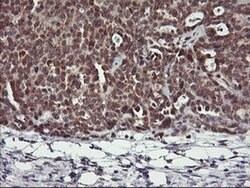

USP10 Mouse anti-Human, Clone: OTI1A10, liquid, TrueMAB™

Ubiquitin is a highly conserved protein that is covalently linked to other proteins to regulate their function and degradation. This gene encodes a member of the ubiquitin-specific protease family of cysteine proteases. The enzyme specifically cleaves ubiquitin from ubiquitin-conjugated protein substrates. The protein is found in the nucleus and cytoplasm. It functions as a co-factor of the DNA-bound androgen receptor complex, and is inhibited by a protein in the Ras-GTPase pathway. The human genome contains several pseudogenes similar to this gene.Specifications

| Flow Cytometry, Immunohistochemistry (Paraffin), Western Blot | |